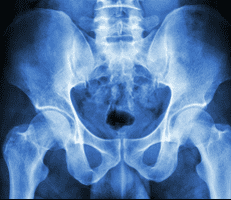

Pelvic Reconstructive Surgery